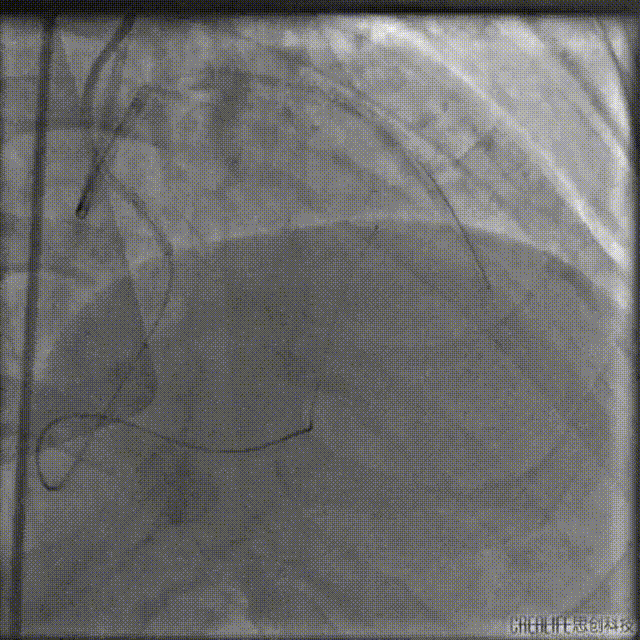

最终造影结果

复查造影未见明显狭窄,TIMI血流3级。